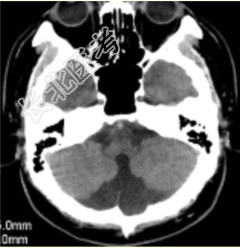

- 单项选择题男性,40岁。走路不稳数年。CT表现如下图。可能的诊断为

A、神经纤维瘤病Ⅰ型

B、Dandy-Walker综合征

C、结节性硬化

D、带状型灰质异位

E、颜面血管瘤综合征